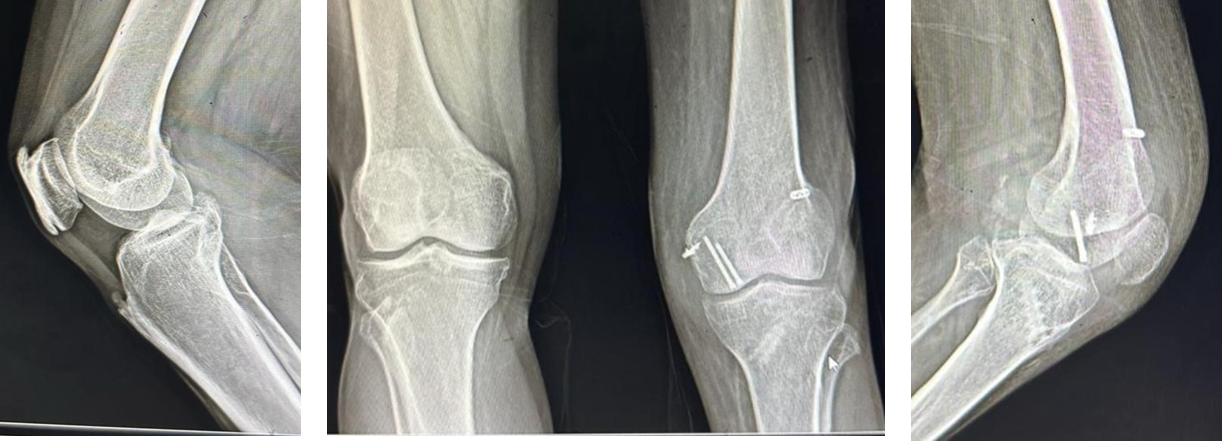

At 4 months, the fracture was well united (Fig. 9) without any subsidence, so full weight bearing was allowed and the brace was discontinued.

Figure 9: Four months post-operative X-rays.